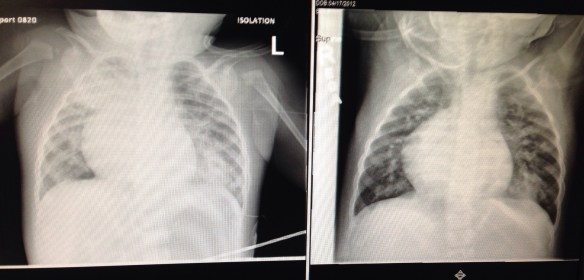

So here is what is going on. The below image is a comparison of Monday’s X-ray vs. today’s X-ray (autocorrect keeps trying to correct “X-ray” to “cray”. That’s totally cray.)

Monday’s is on the right and today’s is on the left.

The cloudy areas have increased – which is the pneumonia. It is looking more like a viral type because it is not responding to the antibiotic. The pneumonia is causing the high fevers. Nothing new has shown up in the blood labs, which is good.